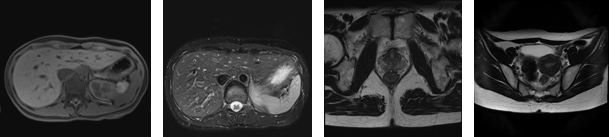

○腹部・骨盤